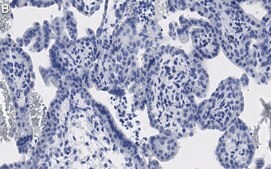

Immunohistochemistry (Paraffin) Analysis: A 1:100 dilution from a representative lot detected ATG7 in human placenta tissue sections.